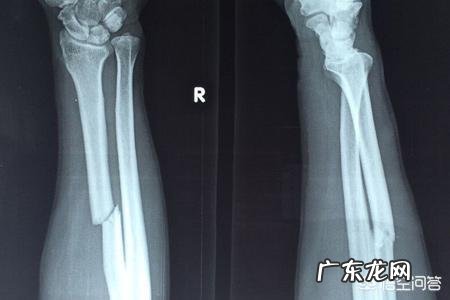

骨折在现在生活比较常见的病症了,在医院经过治疗后回到家里,如何正确的饮食对大部分患者来说,都是一知半解,患者家属怕病人营养不够,每天换着花样盲目进补,今天骨头汤,明天老母鸡汤,后天甲鱼汤,这种情况数不胜数,其实这样吃对患者的骨骼愈合不仅没好处,甚至还有可能导致骨折恢复时间延长 。下面就给大家讲一讲骨折期间应该如何饮食 。

骨折了,经过专业医生的固定和治疗后,就可以回家等待康复了 。一般情况下,骨折的不断愈合会经历三个时期: